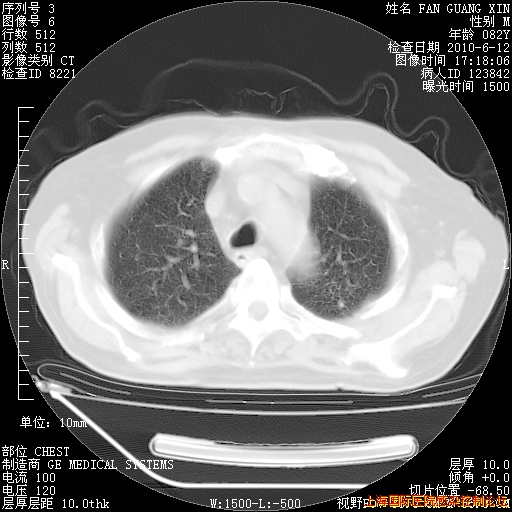

补发6月12日肺部CT肺窗

6月12日肺窗

6月12日纵膈窗